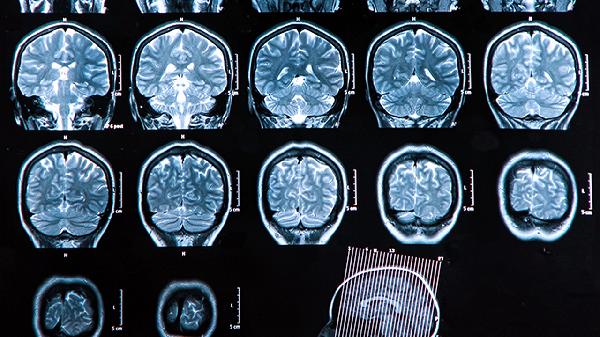

脑溢血后可能出现哪些严重并发症?

脑溢血可能会引发多种并发症,如脑水肿、肺部感染、消化道出血、癫痫发作和深静脉血栓等。脑溢血指的是非外伤性脑组织内血管破裂...